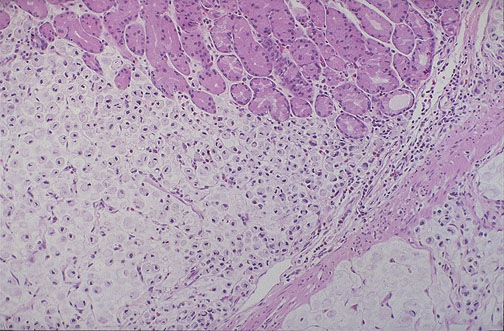

At medium power, normal gastric glands are seen at the top, and infiltrating signet ring cell adenocarcinoma is seen below. This histologic pattern is typical for the diffuse variant of gastric adenocarcinoma which is extensive and infiltrative.